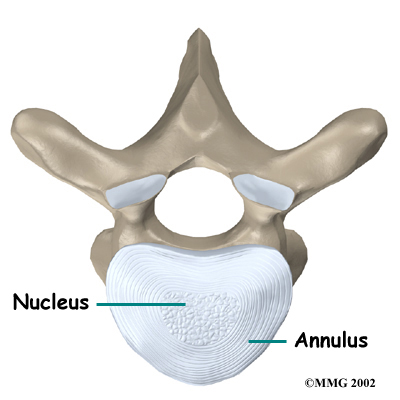

The intervertebral disc is a specialized connective tissue structure that separates the vertebral bodies. The disc is made of . The center, called the nucleus, is spongy. It provides most of the disc's ability to absorb shock. The nucleus is held in place by the annulus, a series of ligament rings surrounding it. Ligaments are strong connective tissues that attach bones to other bones.

Healthy discs work like shock absorbers to cushion the spine. They protect the spine against the daily pull of gravity and during activities that put strong force on the spine, such as jumping, running, and lifting.